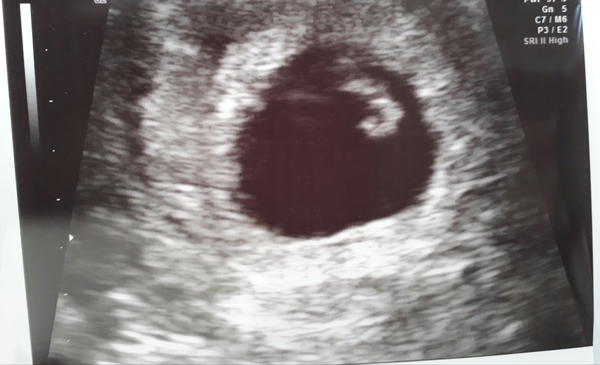

Hi all just had an early scan, from my dates I worked out I was 7+6 today but the sonographer measured me at only 7 weeks so a little concerned as the dates don't make sense and I hope baby isnt on the small side or something. Heartbeat could be seen on the screen but too early for her to pick up the rate. Should I be worried?

Also anyone know much about the ramzi theory? I've read about it but can't work it out.. Any guesses?

Babies due in April 2018